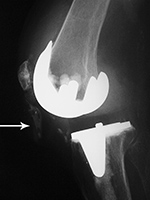

Left total knee prosthesis patellar button dislocation |

Right total knee prosthesis patellar button dislocation |

The patellar button is dislocated superiorly (arrow). |

The patellar component (button) is dislocated inferiorly (arrow) |